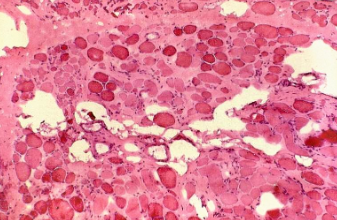

No entanto, em pessoas com distrofia muscular de Duchenne, o corpo não produz ou produz uma quantidade insuficiente de distrofina. Como resultado, as fibras musculares tornam-se fracas, se degeneram e são gradualmente substituídas por tecido adiposo (gordura) e fibrótico (cicatrizes), assim o músculo perde muito de suas capacidades de contração.

Veja um músculo saudável e um músculo com distrofia muscular de Duchenne

Fonte: anatpat.unicamp.br